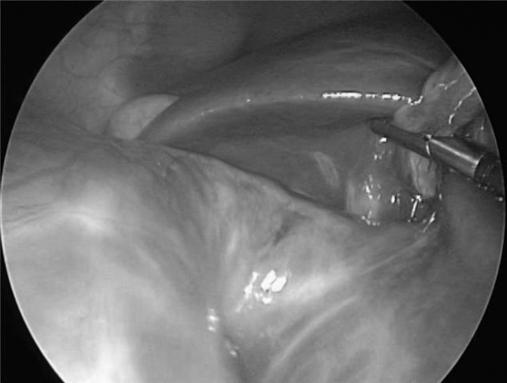

Benign congenital liver cysts are rare in the pediatric population and often present a challenge in the diagnosis. Therefore, with recent advances in the field of minimally invasive surgery, this technique may be ideal in achieving both diagnosis and curative resection. We describe the case of a 2-month-old female initially referred for an antenatal ultrasound in the third trimester revealing a 7-cm intraabdominal cystic lesion of unknown origin. She was found to have a 10-cm hepatic cyst successfully treated by laparoscopic surgery. Our approach consisted of complete cyst excision along with its attached hepatic parenchyma. We recommend this technique as safe and feasible.